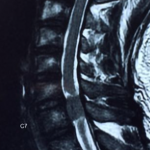

After detailed questioning, it is obvious that Mr. Lin’s problem has caused cauda equina syndrome. There may be a tumor in the spinal cord or a severe lumbar disc herniation compressing the spinal cord. Immediately arrange the patient to take a full spine MRI, and immediately after 2 hours after reading the scans, it turned out that the patient had a 1.6cm tumor at the 6/7 spinal canal position of the cervical spine and severely compressed the spinal cord. He was immediately referred to a neurosurgeon on the same day and arranged to be admitted to the hospital that night, and the cervical cord tumor was removed the next day by surgery. After the operation, the patient’s foot pain and numbness gradually improved.

Because the tumor area is relatively large, the compressed spinal cord is more resistant to compression, so even after it is relieved, there will be some nerve damage. 7 weeks after the operation, the author arranged for him to come back for continued postoperative decompression treatment that helps the damaged nerves to .slowly recover the function